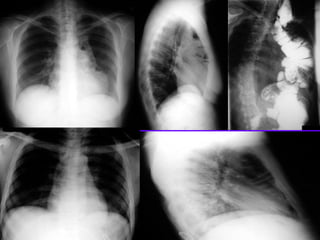

Left Upper Lobe Consolidation

Density in the left upper lung field

Loss of silhouette of left heart margin

Density in the projection of LUL in lateral view

Air bronchogram in PA view

No significant loss of lung volume

Consolidation / Lingula

Density in left lower lung field

Loss of left heart silhouette

Diaphragmatic silhouette intact

No shift of mediastinum

Blunting of costophrenic angle

Lateral

Lobar density

Oblique fissure not

significantly shifted

Air bronchogram

Consolidation Left Lower Lobe

Left heart silhouette intact

Loss of diaphragmatic silhouette